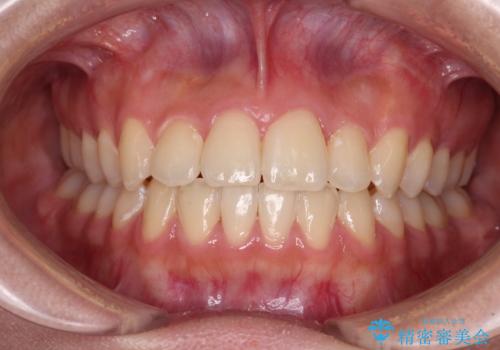

【モニター】左右のクロスバイトをインビザラインできれいに改善